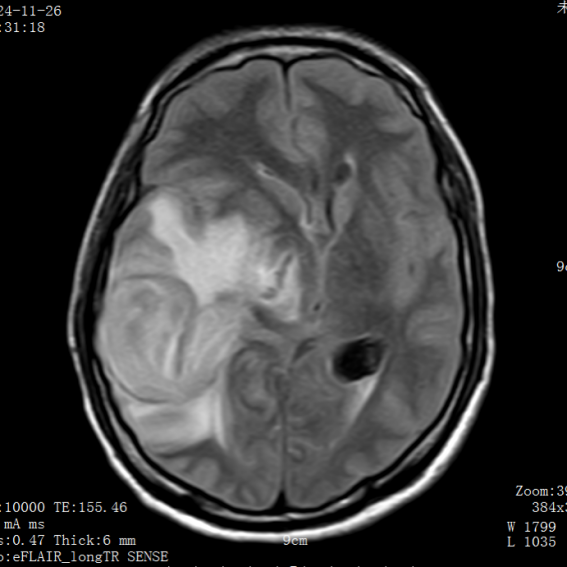

影像医学科王樱花主任阅片后,考虑脑脓肿合并急性脑疝。脑疝是颅内压增高最危险的并发症之一,堪称大脑“断电”前兆。当颅腔内某一部分压力骤增,脑组织被挤压到另一个腔室,压迫脑干,可迅速导致呼吸心跳停止。而脑脓肿是一种由细菌、真菌或寄生虫引起的颅内化脓性感染,若不及时处理,脓肿增大压迫脑干,后果不堪设想。

该患者MR显示:右侧顶枕叶类圆形低密度影,周围水肿明显,中线结构左移超过1cm脑室受压变窄,环池显示不清,提示小脑幕切迹疝早期,已处于濒死边缘。